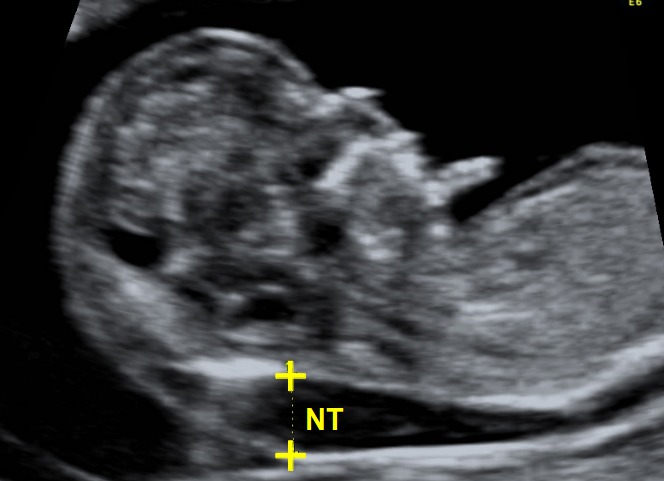

Nuchal Translucency Screening (NT)

UCSF Medical Center is one of the few centers nationwide to offer nuchal translucency screening (NT) screening, a new, non-invasive test performed early in pregnancy to identify an increased risk for Down syndrome and other birth defects. NT screening is performed between 11 and 14 weeks of pregnancy. It is offered to women of all ages. The screening is done via a high-resolution ultrasound exam of the nuchal area — a fold of skin at the back of the neck of the fetus. The results are combined with the mother's age to determine an adjusted risk for Down syndrome. The rate of detection for Down syndrome is about 80 percent. Based on the results, a woman has the option of undergoing CVS or amniocentesis for diagnosis.